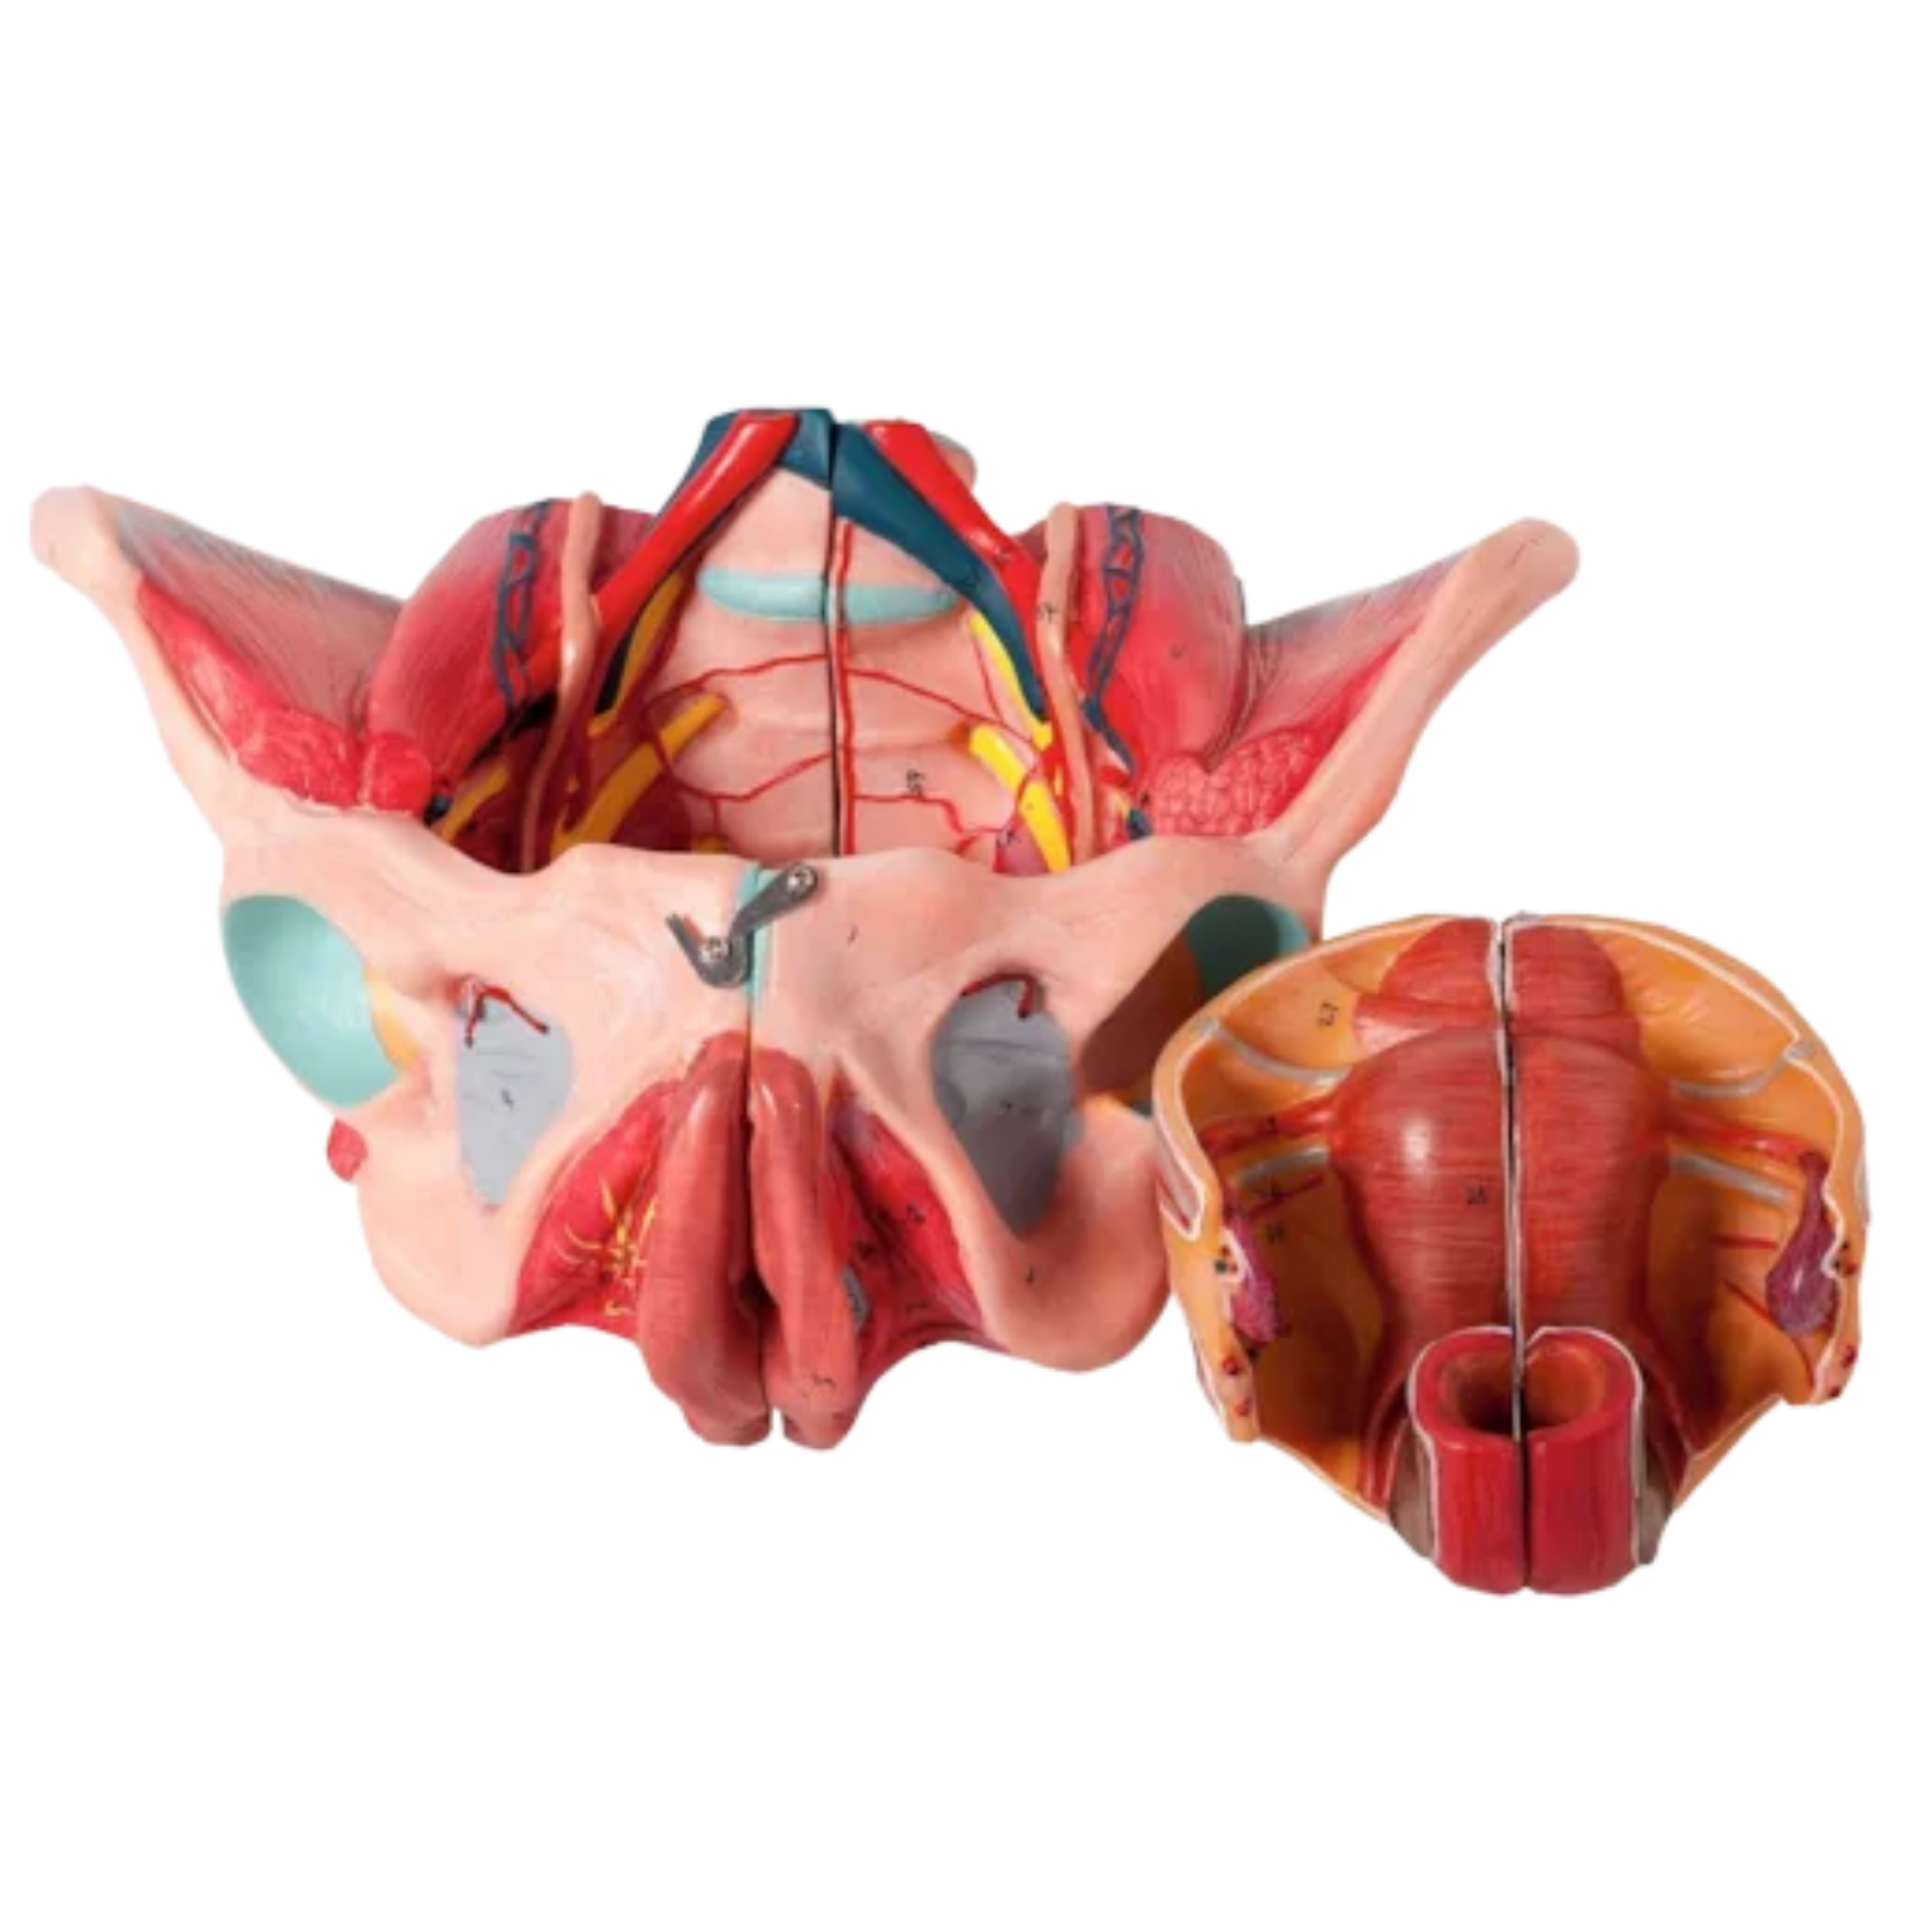

Tratamentos para incontinência urinária, dor pélvica e pós-parto

Tratamentos personalizados para ajudar você a recuperar a sua saúde e viver com mais bem-estar.

Recupere sua confiança e a sua qualidade de vida! Tratamento fisioterapêutico especializado para incontinência urinária em mulheres de todas as idades, com técnicas seguras e eficazes.

A fisioterapia pélvica é uma especialidade da fisioterapia que trata disfunções relacionadas ao assoalho pélvico, como incontinência urinária, dor pélvica, prolapso de órgãos e disfunções sexuais. Ela tem como objetivo fortalecer e reabilitar a musculatura da região íntima, promovendo saúde, bem-estar e qualidade de vida.

Mulheres que sofrem com perdas urinárias, dor nas relações, bexiga hiperativa, flacidez pós-parto, ou dificuldade de controle urinário podem se beneficiar da fisioterapia pélvica feminina. Também é indicada na gravidez e pós-parto, ajudando na preparação e recuperação do corpo.